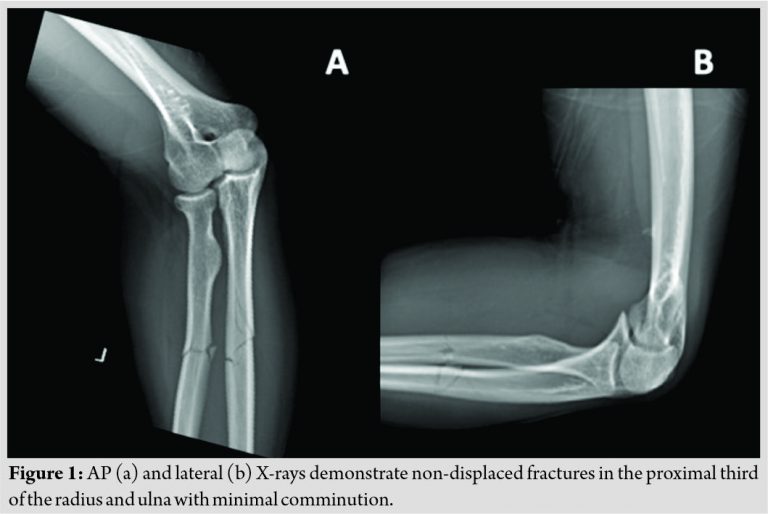

A 23-year-old, Caucasian, right hand dominant male, otherwise healthy, was seen in the emergency department after a skateboard accident. He reported falling onto his dorsal left proximal forearm and experienced immediate pain in the area without other injuries. Physical examination was notable for tenderness over the proximal radius and ulna and limited pronosupination secondary to pain. Plain radiographs demonstrated non-displaced but slightly comminuted, short oblique fractures of the proximal third of the radius and ulna (Fig. 1a, b). After discussion with the patient and his family, the decision was made to place the patient in a long arm cast (Fig. 2a, b) and follow-up in the clinic in 1 week.